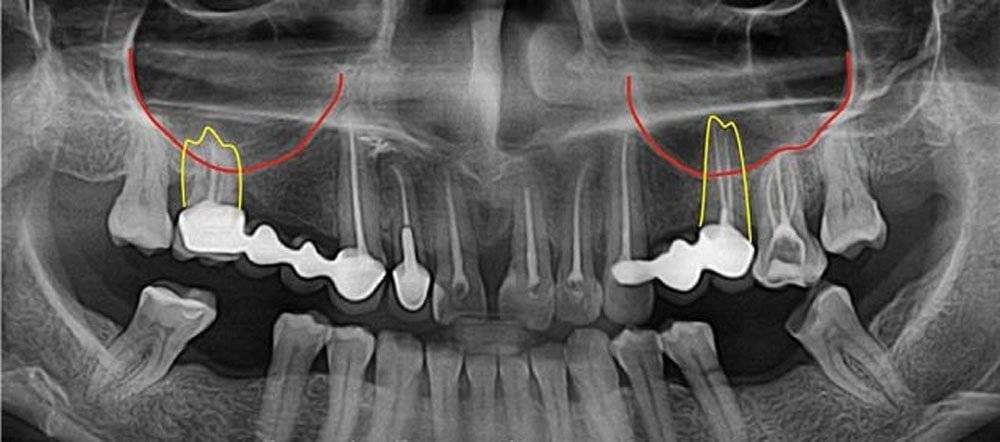

Медицинские Исследования: Кортикальная Пластинка на ОПТГ

Раздел: Кадры-подсказки